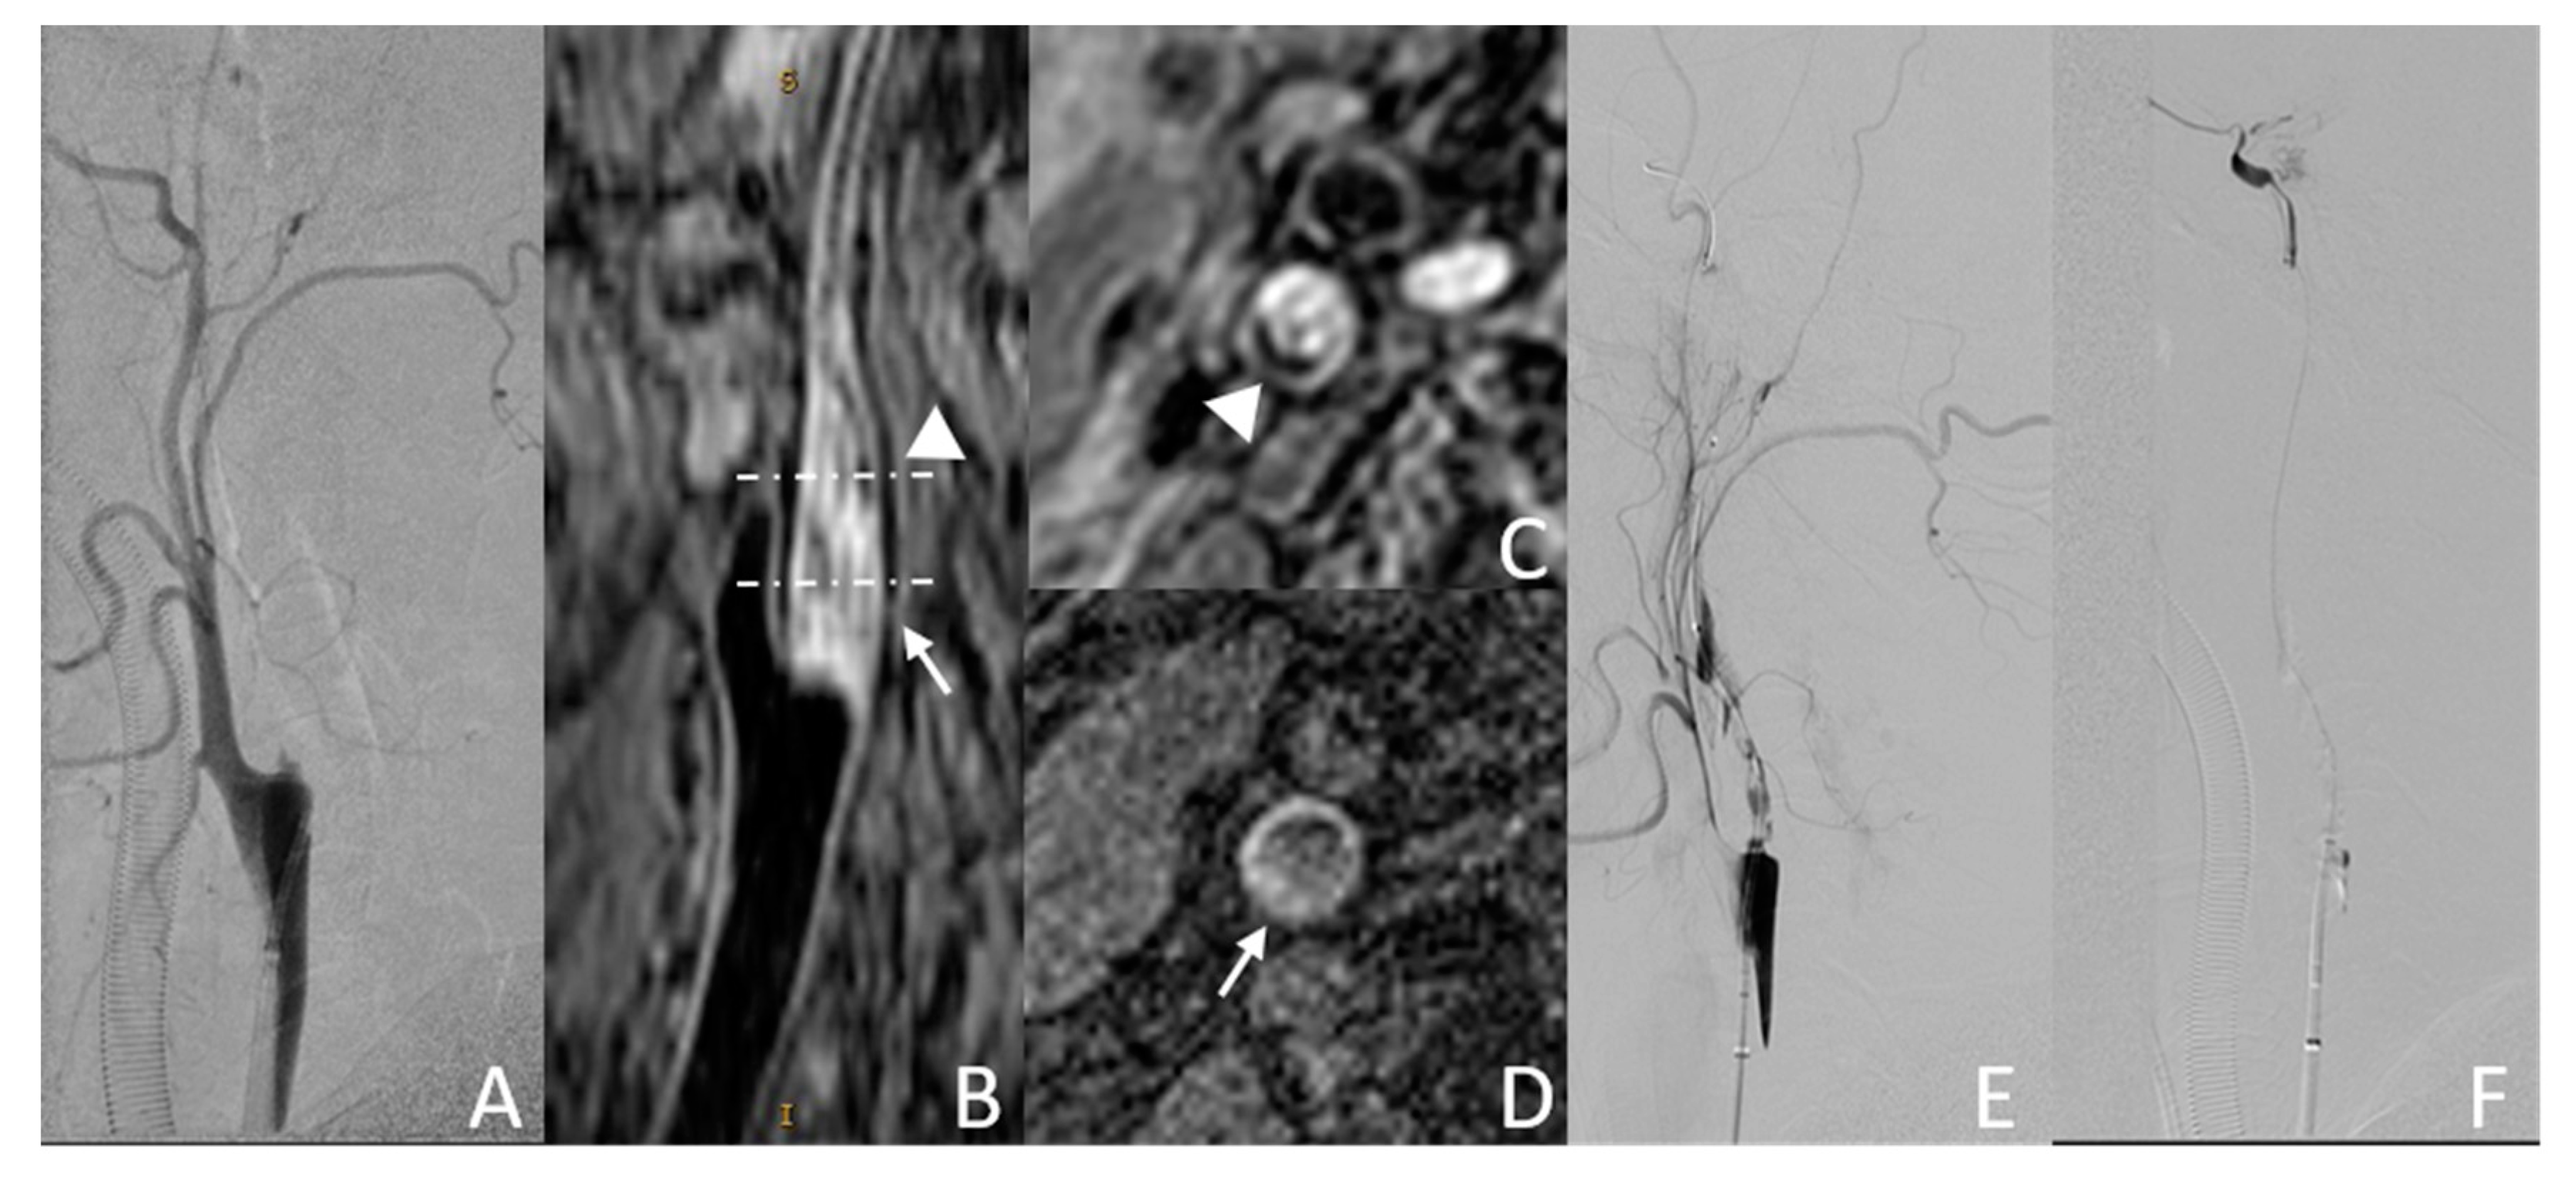

3.3.1. Example Case 1